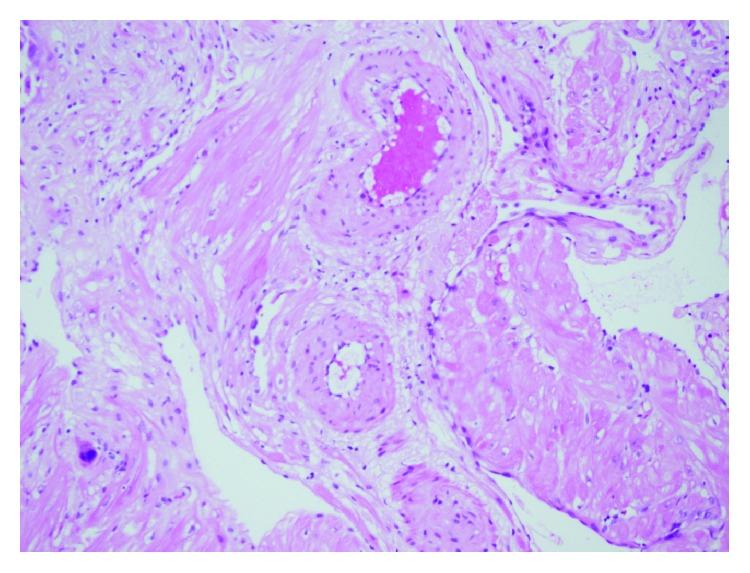

孕早期与孕中期子宫动脉多普勒测速与胎盘床组织病理学之间的相关性

Correlation between First and Second Trimester Uterine Artery Doppler Velocimetry and Placental Bed Histopathology.

Aim. To evaluate the relationship between uterine artery Doppler indices and placental bed histopathology independent of clinical outcome. Materials and Methods. Uterine artery measurements were performed to 510 pregnant women who had come for routine antenatal care in 11-14th and 20-24th weeks. Placental bed biopsies from 141 cases were taken during cesarean section. Physiological changes and abnormal placental histology findings were investigated and compared with Doppler findings. Results. 116 biopsies were accepted as adequate biopsy and included in the study. Physiological changes were seen in 100 biopsies. Statistically significant higher PI and RI values in second trimester and higher notch rate in both trimesters were detected in the abnormal placental histology group (P < 0,001). Conclusion. Strong relationship between uterine artery Doppler indices and preeclampsia or intrauterine growth retardation has been shown in previous studies. In our study, we concluded that there is significant relationship between Doppler findings and placental bed histopathology independent of clinical course.

目的。评估子宫动脉多普勒指数与胎盘床组织病理学之间的关系,而不考虑临床结局。材料与方法。对510名在孕11 - 14周和20 - 24周前来进行常规产前检查的孕妇进行子宫动脉测量。在剖宫产时从141例病例中获取胎盘床活检组织。研究生理变化和异常胎盘组织学发现,并与多普勒检查结果进行比较。结果。116份活检组织被认为是足够的活检样本并纳入研究。100份活检组织出现生理变化。在异常胎盘组织学组中,检测到孕中期的搏动指数(PI)和阻力指数(RI)值在统计学上显著更高,且两个孕期的切迹率均更高(P < 0.001)。结论。先前的研究表明子宫动脉多普勒指数与子痫前期或胎儿生长受限之间存在密切关系。在我们的研究中,我们得出结论,多普勒检查结果与胎盘床组织病理学之间存在显著关系,且与临床过程无关。